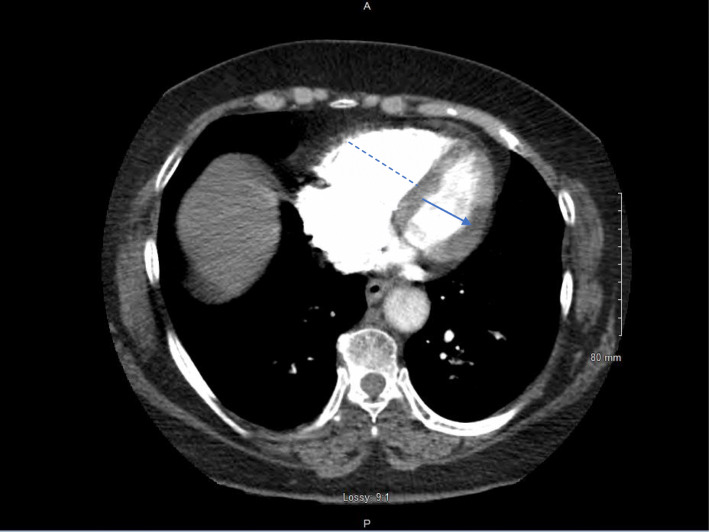

Fig. 2.

CT scan shows the short axis of the right ventricle (dashed line) is wider than the left ventricle (solid line), a condition called RV strain and is caused by acute pulmonary embolism